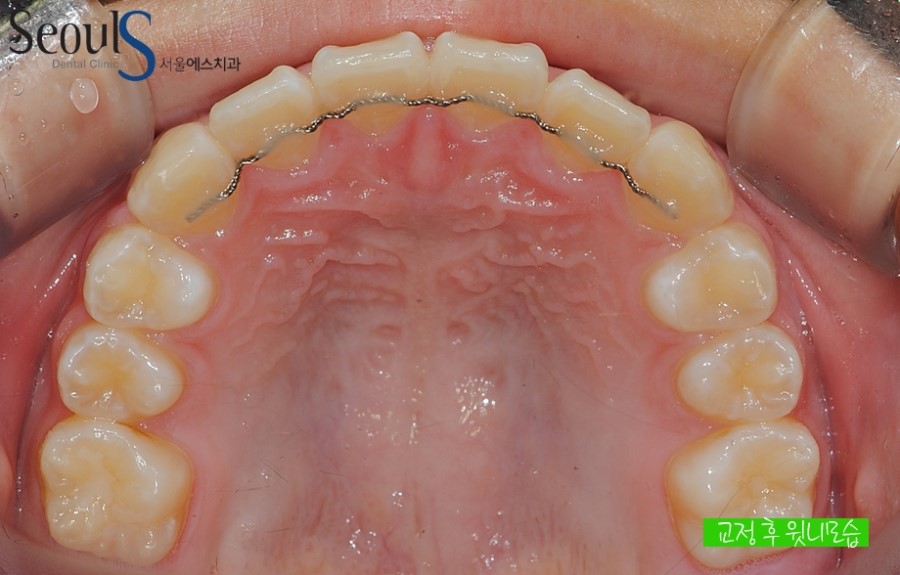

교정 후 윗니 모습입니다

교정 전 삐뚤었던 윗니가

가지런해진 모습입니다